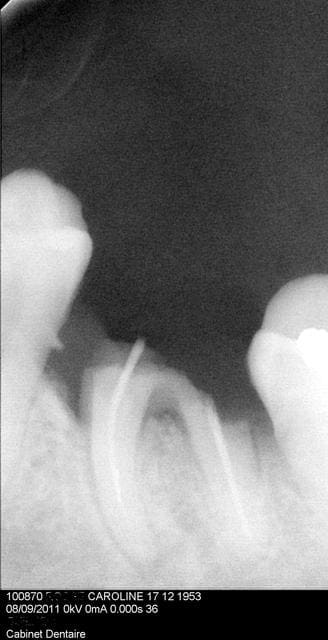

Images qct94b - Eugenol

themumbly

15/09/2011 à 12h18

Patiente sous LYTOS depuis 2 ans...je ne sais pas quoi faire, mais il faudra bien l'extraire cette dent ( infection )

Vos avis??